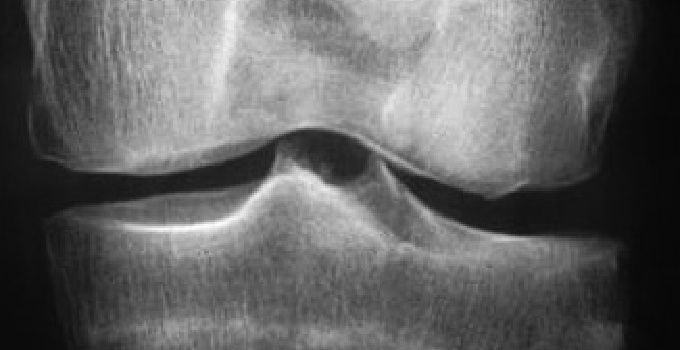

Les radiographies standard sont réalisées en position debout, bilatérales et comparatives, avec des clichés de face et de profil, en schuss, comprenant des incidences fémoropatellaires. Elles permettront l’étude des interlignes articulaires, d’observer un pincement et d’en évaluer l’importance et l’éventuelle aggravation dans le temps, confirmant fréquemment une arthrose fémorotibiale le plus souvent interne, montrant une éventuelle liseré calcique (chondrocalcinose), une destruction ostéo-articulaire (dommages structuraux de la polyarthrite rhumatoïde) avec géodes et ostéolyse, l’affaissement de l’interligne (ostéonécrose).